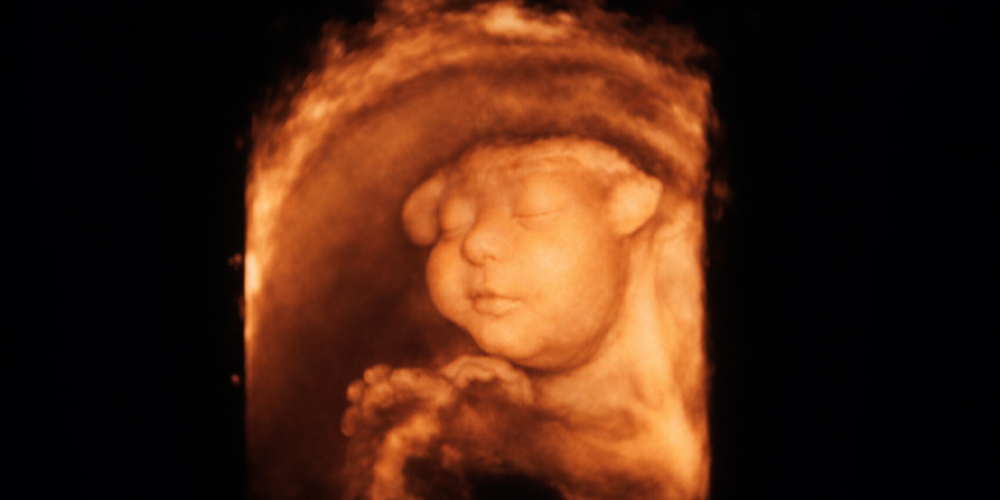

Ağır gelişme anomalileri:

Kafatası gelişmeyebilir ( Akranii).

Beyin dokusu açıkta kalabilir ( Egzensefali).

Beyin dokusu gelişmeyebilir ( Anensefali).

Beyin dokusunun içindeki ayrıntılarda eksiklikler olabilir:

Sıvı dolu keseciklerin aşırı genişlemesi olabilir ( Ventrikülomegali).

Beyinciğin bir kısmı gelişmeyebilir ( Vermis agenezisi).

Kafatası içinde kistik (sıvı dolu) veya solid (katı) tümoral oluşumlar gelişebilir ( Araknoid kistler, Dandy-Walker Sendromu, Corpus Callosum Agenezisi, Galen Veni Anevrizması, Megasisterna Magna, Teratom).

Sırttaki kapanamama sorunu nedeniyle beyin sapının sıkışması ve beyinde su toplaması ( Arnold-Chiari Malformasyonu).

***

Bu anomalilerin önemli bir kısmı hayatla bağdaşmaz. Yani doğduktan kısa bir süre sonra kaybedilirler. O durumda gebeliğin düşükle sonlandırılması kolay karar verilebilen en kestirme yoldur. Diğerlerinde hastalığın akıbetine ve ağırlığına göre aileye bilgi verilir. Ve ailenin tercihleri yönünde, tabii ki meslek ilke ve etiği çerçevesinde bir yol seçilir.